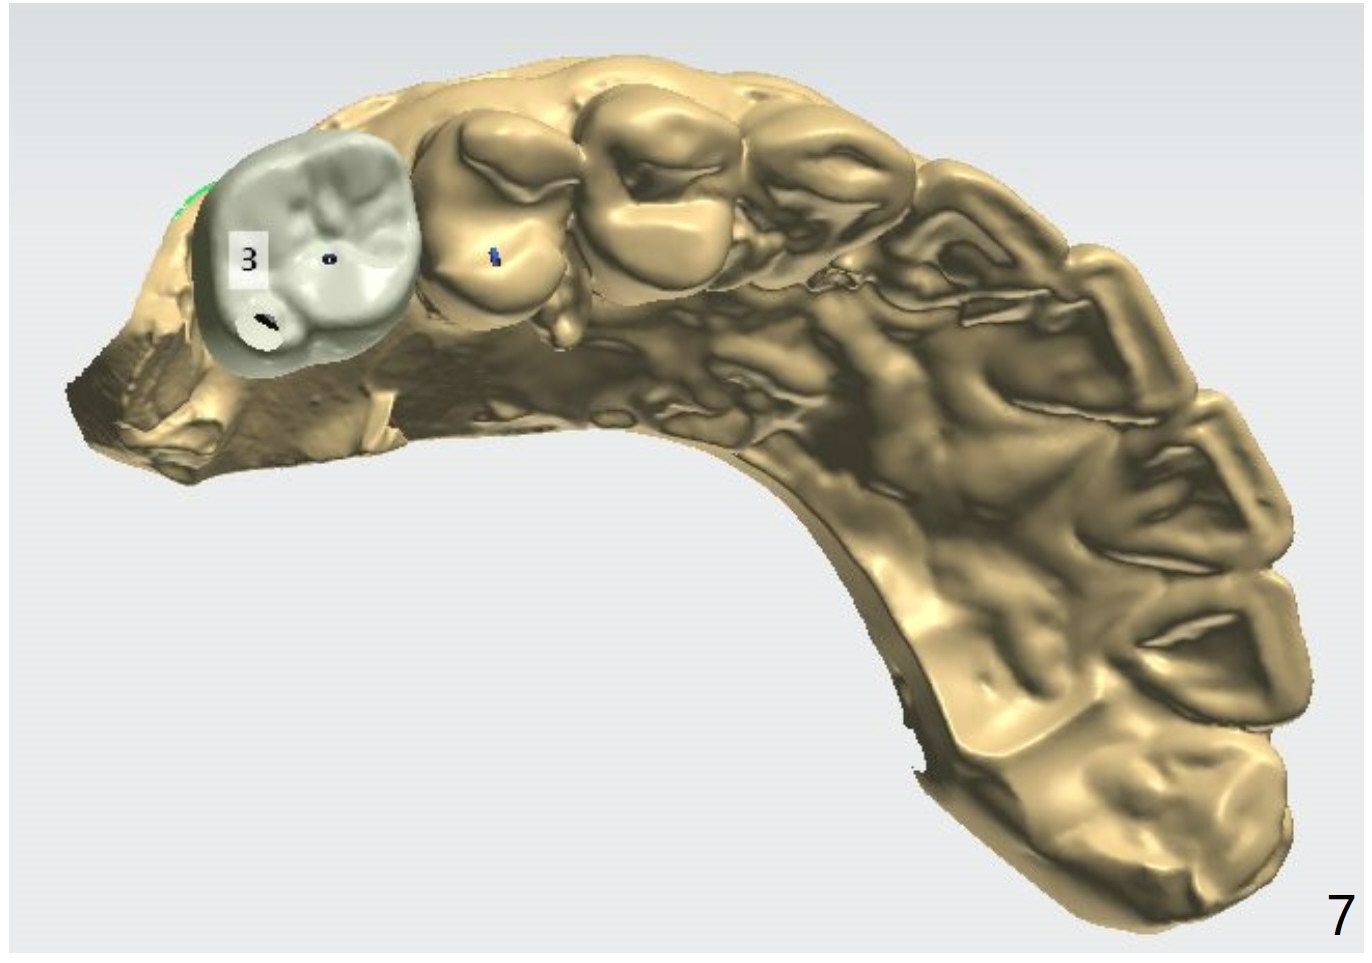

66岁男缺失右上,右下第一磨牙许久,需要上颌窦提升。Because of sinus lift, make a little sticky bone, considering autogenous bone from #30 and 3 osteotomy sites. Tube x1.